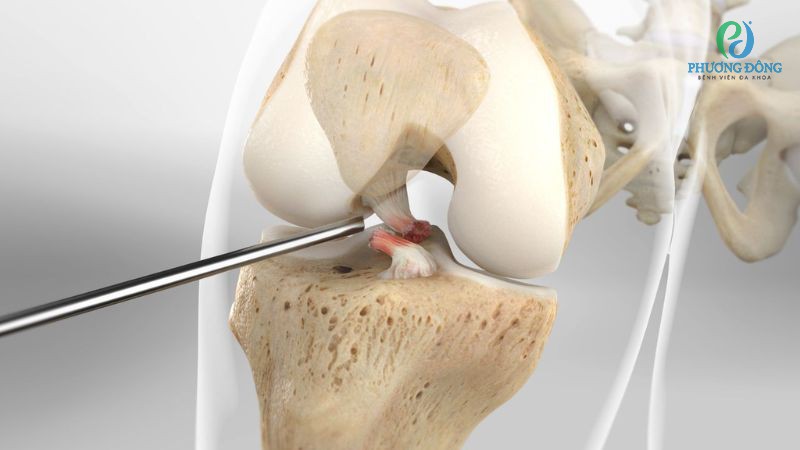

Mổ nội soi tái tạo dây chằng chéo trước là kỹ thuật hiện đại, tiến hành nhằm mục đích thay thế dây chằng chéo bị đứt hoặc tổn thương. Phương pháp có khả năng khôi phục tối đa đặc điểm giải phẫu, chức năng vận động khớp gối, giúp người bệnh sớm trở lại nhịp sống sinh hoạt thường ngày.

Trong chuyên ngành chấn thương chỉnh hình, phẫu thuật nội soi được coi như bước tiến mới nhờ khả năng xâm lấn tối thiểu, ít chảy máu, giảm đau sau mổ. Từ đó tối ưu hiệu quả hồi phục hậu phẫu, hạn chế tối đa các tổn thương thứ phát lên các mô mềm xung quanh.

Đối với nội soi khớp gối, bác sĩ chỉ cần rạch một vài đường nhỏ trên da để đưa dụng cụ chuyên dụng vào bên trong. Các thiết bị này giúp bác sĩ quan sát chi tiết, rõ nét cấu trúc cũng như tổn thương bên trong để can thiệp và xử lý tổn thương một cách chính xác.